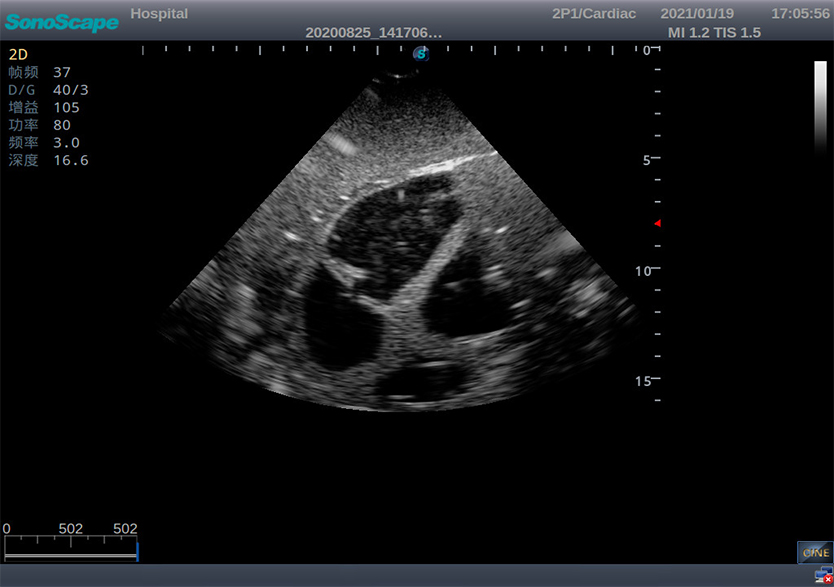

影像系列